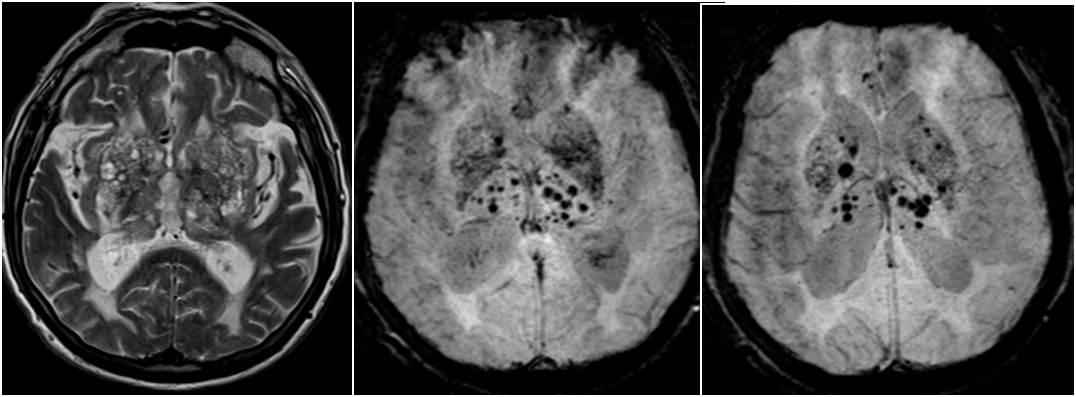

Демиелинизирующие заболевания мозга: МРТ изображения